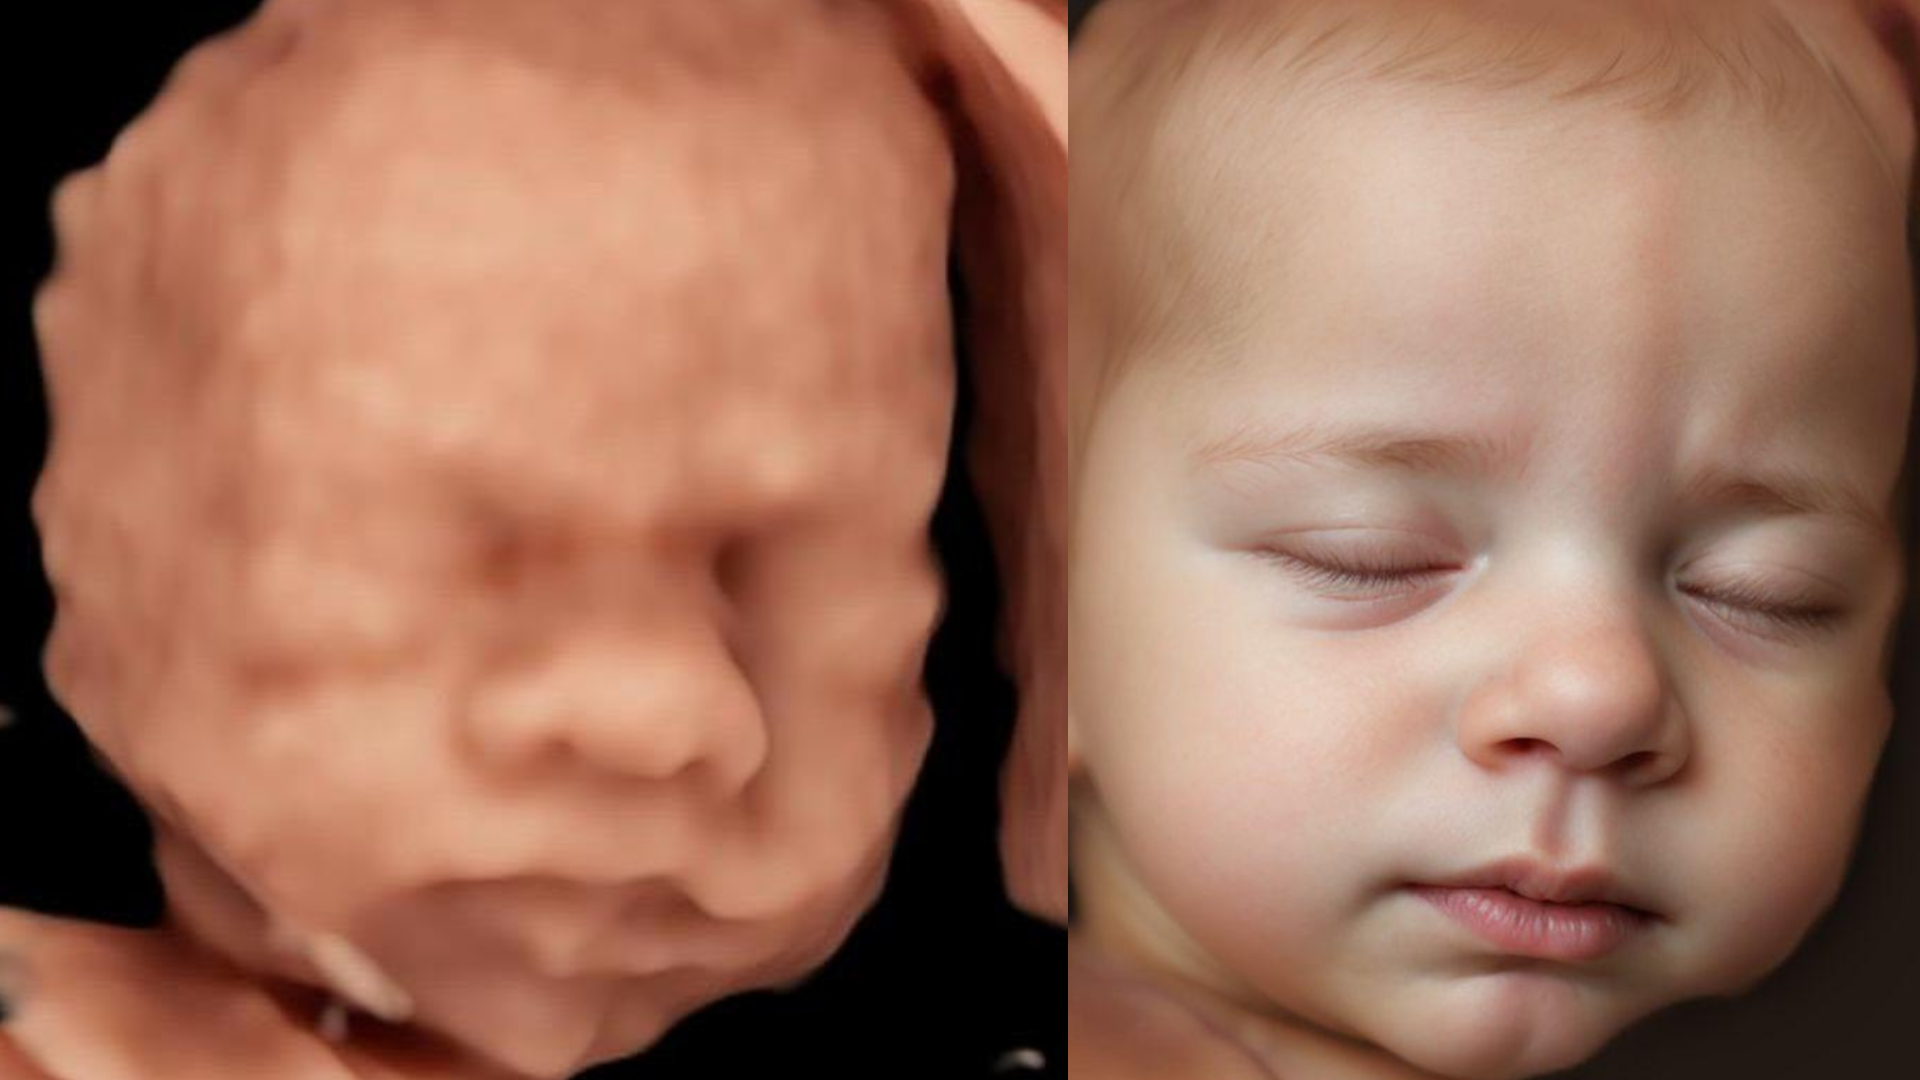

6D ECHO

Hoe werkt het?

Dit wordt gemaakt van jouw 3D/4D echo (ook al werd deze niet bij ons gemaakt) met de meest geavanceerde technologie om zo elk detail van het gezichtje in beeld te brengen.

Maak je afspraak voor een 3D/4D echo en kies onmiddellijk na de sessie de echo die jullie het leukste vinden.

Indien jullie al een 3D/4D echo hebben laten maken, mail je je leukste 3D/4D echo door naar info@littlemiraclehoekschewaard.nl

Als we de foto goed ontvangen hebben, krijg je een bevestiging met de betaalgegevens.

Wanneer we de betaling goed ontvangen hebben, gaan we er mee aan de slag.

De gemiddelde levertijd is tussen 5 en 7dagen.

Voorwaarden:

*digitale 4D echo van goede kwaliteit

*het gezichtje moet zo duidelijk mogelijk zichtbaar zijn (dus zo weinig mogelijk voorliggende delen zoals placenta of navelstreng)